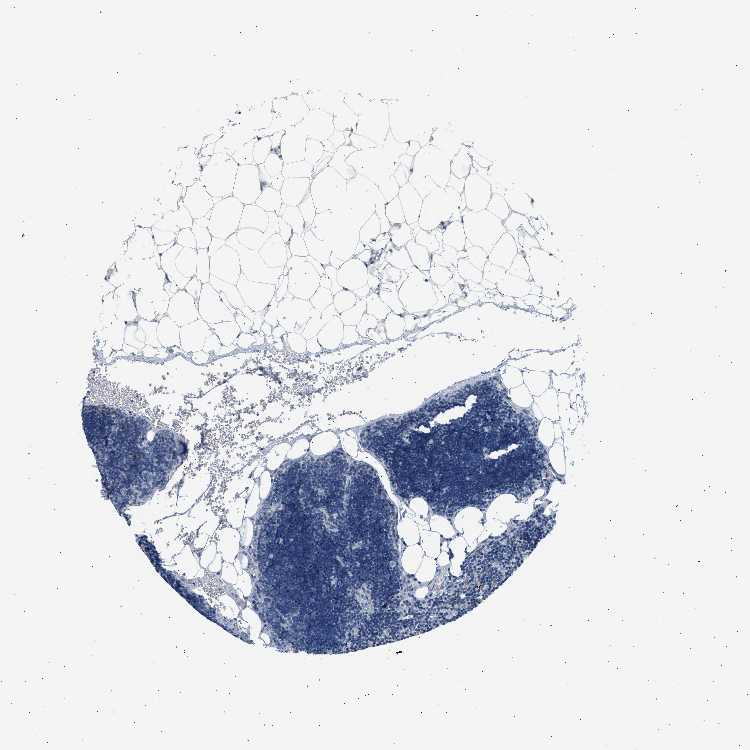

LYMPH NODE - Antibody stainingi

Antibody staining in the annotated cell types in the current human tissue is reported as not detected, low, medium, or high, based on conventional immunohistochemistry profiling in selected tissues. This score is based on the combination of the staining intensity and fraction of stained cells.

Each image is clickable and will lead to virtual microscopy that enables deeper exploration of all samples and also displays staining intensity scores, fraction scores and subcellular localization as well as patient and tissue information for each sample.

Antibody HPA017646

Germinal center cells Not detected

Non-germinal center cells Not detected